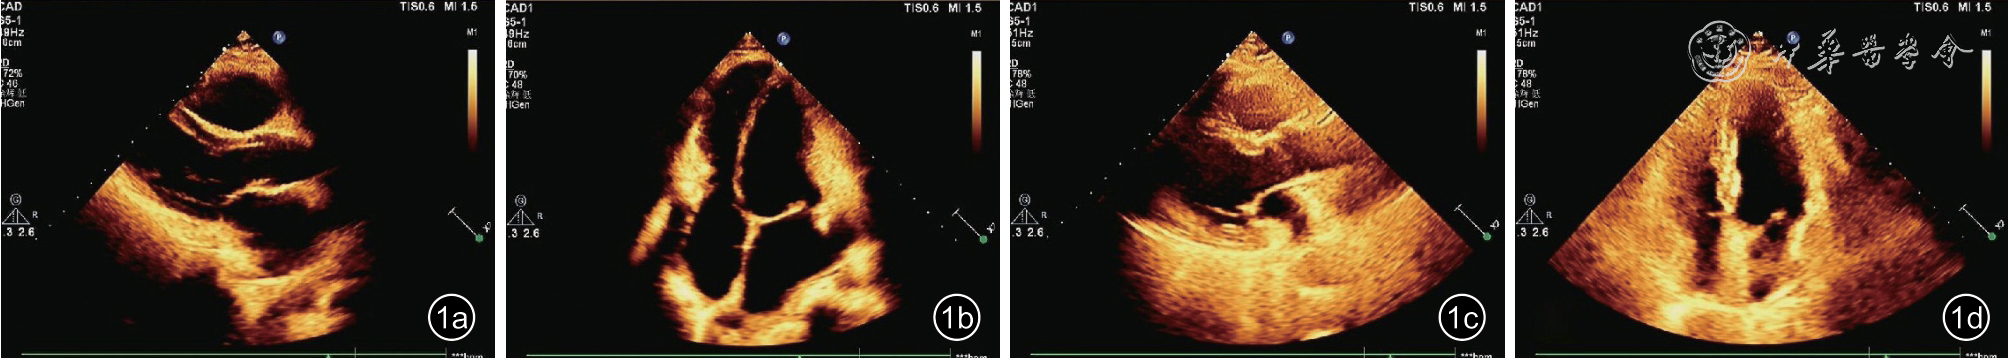

与超声诊断组相比,漏诊组心脏形态改变较不明显(图1),漏诊组心房增大及心室缩小均不明显,2 组左心房前后径、右心房横径及左心室内径差异有统计学意义(P 均<0.05),漏诊组左心室质量指数较大、下腔静脉内径较窄(P<0.05)。超声诊断组中较高比例的患者有室间隔“弹跳征”(81.7%,67/82)及二尖瓣前向E-E 变化率>25%(59.8%,49/82)。2 组左心室射血分数差异无统计学意义,但漏诊组二尖瓣间隔瓣环舒张早期速度(e')较低(P=0.034,表2)。

图1 缩窄性心包炎超声诊断与超声漏诊图像。图a、b 分别为超声心动图诊断的缩窄性心包炎左心室长轴及心尖四腔二维图像;图c、d 分别为超声心动图漏诊的缩窄性心包炎左心室长轴及心尖四腔二维图像